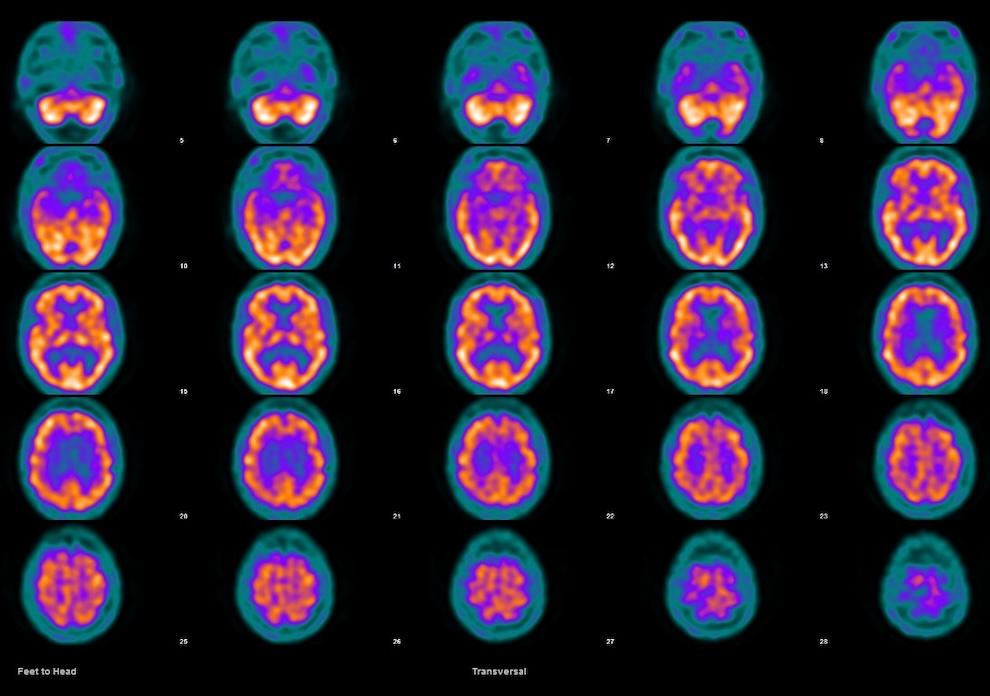

El SPECT (Tomografía por Emisión de Fotón Único) es una técnica de imagen médica que permite observar cómo funciona el cerebro, no solo cómo se ve.

A diferencia de otras pruebas como la resonancia magnética o el TAC, que muestran la forma y estructura del cerebro, el SPECT muestra su actividad y el flujo de sangre en las distintas zonas cerebrales.

El SPECT cerebral detecta cambios en la actividad cerebral basándose en la distribución la sangre en las distintas zonas del cerebro: cuando una parte del cerebro está más activa, necesita más oxígeno y nutrientes, por lo que recibe mayor flujo sanguíneo.

Así, si una zona reduce su actividad (por ejemplo, debido a una demencia o un daño cerebral) su riego sanguíneo también disminuye.

Esta sustancia viaja por la sangre hasta el cerebro y se acumula en las áreas según su nivel de actividad: cuanto más activa está una región cerebral, más radiofármaco capta. Las zonas menos activas retienen menos cantidad.

Después, una cámara especial llamada gammacámara gira lentamente alrededor de la cabeza y capta la radiación que emite el radiofármaco.

Con estas señales, un ordenador genera imágenes tridimensionales (3D) que reproducen la distribución del flujo sanguíneo y muestran cómo está trabajando cada parte del cerebro.

El resultado es una especie de mapa funcional del cerebro, donde los colores cálidos (rojo y naranja) muestran las áreas más activas y los fríos (azul y verde) las zonas con menor actividad.